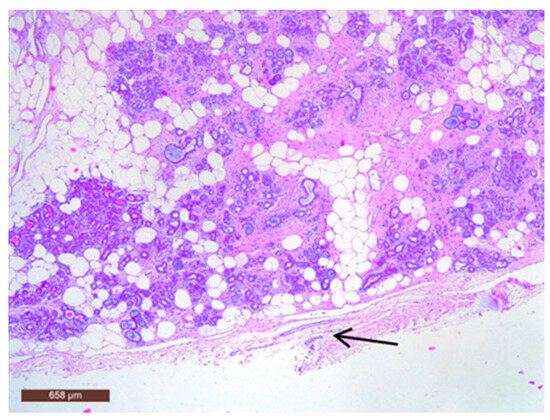

Adipose tissue in the hamartoma may be prominently proliferative (Figure 11), which can complicate the differential diagnosis with a lipoma on ultrasound. Conversely, the adipose component can also be nearly absent.

In some instances, fibrous tissue may predominate (Figure 12). Additionally, three cases in our study were associated with chronic inflammation. In the series of 13 cases, no cases with associated malignancy were observed.

Figure 11. Hamartoma with fat cells interspersed within the lesion (HE ×40).

Figure 12. Hamartoma with prominent fibrous tissue (HE ×40).